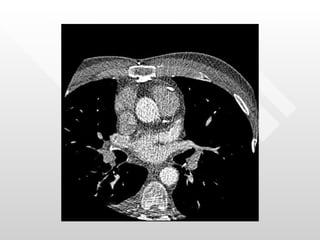

Normal pericardial thickness Multiple adhesions between the pericardium and the heart RV directly below the sternum

Normal pericardial thicknessMultiple adhesions between the pericardium and the heart RV directly below the sternum